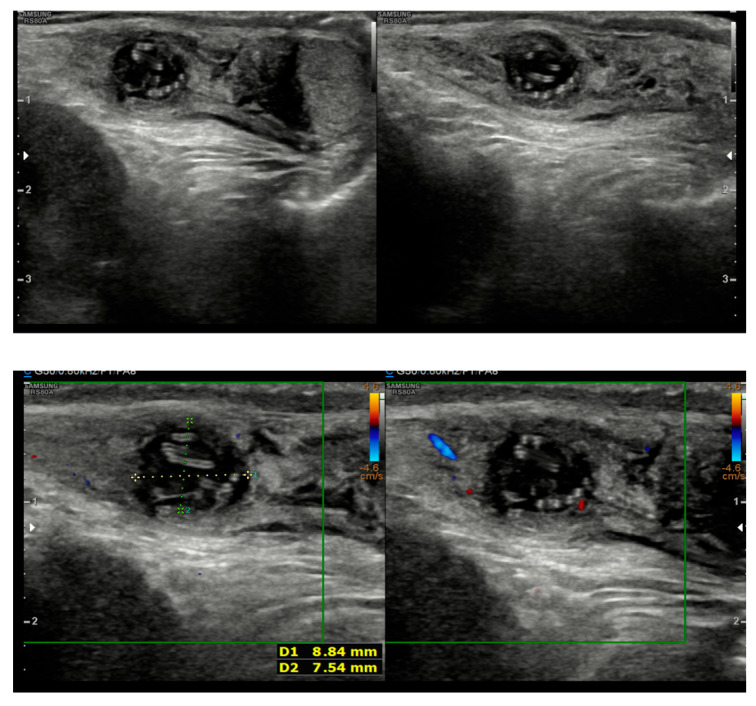

我们报告的情况下,一个5岁的男孩从一个斯里兰卡移民家庭在卡塔尼亚,意大利,诊断为Dirofilaria再感染精索。患儿表现为左侧腹股沟疼痛和肿胀。初步评价提示是睾丸附睾炎,用阿莫西林/克拉维酸盐和非甾体抗炎药治疗不成功。当症状加重时,考虑Morgagni棘球体扭转。探查性手术发现左侧精索有一个坚固的肿块。切除病变的组织病理学检查显示肉芽肿性炎症反应中有蠕虫碎片。随后的PCR分析检测到D. repens DNA。手术切除肿块后,病人完全康复。鉴于人类双丝虫病发病率的增加,在鉴别诊断不明原因的皮下或腹股沟结节时应考虑repens,特别是在有相关旅行史的患者中。该病例强调了准确诊断的重要性,以避免不必要的侵入性手术或延长抗菌药物治疗。这是意大利报告的最年轻的生殖器感染儿科病例之一,意大利占欧洲病例的一半。

We report the case of a 5-year-old boy from a Sri Lankan migrant family in Catania, Italy, diagnosed with a Dirofilaria repens infection in the spermatic cord. The child presented with pain and swelling in the left inguinal area. Initial evaluation suggested orchiepididymitis, which was treated unsuccessfully with amoxicillin/clavulanate and NSAIDs. As symptoms worsened, torsion of the Morgagni hydatid was considered. An exploratory surgery revealed a firm mass in the left spermatic cord. Histopathological examination of the excised lesion showed fragments of a helminth within a granulomatous inflammatory reaction. Subsequent PCR analysis detected D. repens DNA. The patient fully recovered after surgical excision of the mass. Given the increasing incidence of human dirofilariasis, D. repens should be considered in the differential diagnosis of unexplained subcutaneous or inguinal nodules, especially in patients with a relevant travel history. This case highlights the importance of accurate diagnosis to avoid unnecessary invasive procedures or prolonged antimicrobial therapies. It represents one of the youngest pediatric cases with genital involvement reported in Italy, a country that accounts for half of the cases in Europe.